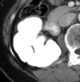

Focal calcification in kidney

Renal cell carcinoma

Simple renal cyst